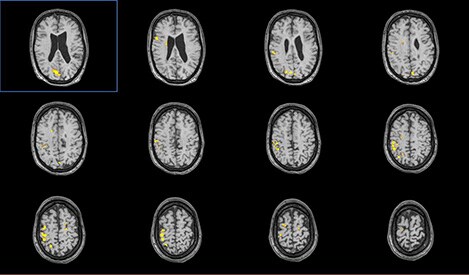

Цель: Апробация и внедрение в клиническую практику современных методик фМРТ и DTI для оценки структурных и функциональных изменений при нарушениях движения у детей. Описание проекта: Для Детского Церебрального Паралича характерно наличие незначительных структурных повреждений [1], при этом неясна их связь с нарушениями двигательных функций. фМРТ позволяет выявить зоны активации мозга при выполнении движений и оценить сложность выполнения задания по объему зон активации (Рис 1). МР-трактография позволяет исследовать структуру и диффузионные характеристики проводящих путей мозга (Рис 2). МР-волюметрия также позволяет оценить объем основных структур мозга и выявить аномалии развития, кортикальные дисплазии и патологии белого вещества мозга (Рис 3.). Результаты: Проведена клиническая апробация предложенных методик. Результаты представлены на медицинских неврологических конгрессах.